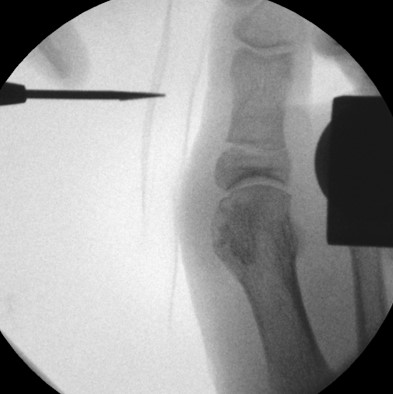

• Notwendigkeit der intraoperativen Bildvestärkerdiagnostik.

• Bildverstärker.

Operationstechnik (Text und Fotos)

• Überkorrektur 910: Eine Überkorrektur kann intraoperativ rückgängig gemacht werden, indem unter Bildwandlerkontrolle die Osteotomie nochmals "aufgedehnt" und die Korrektur verringert wird.